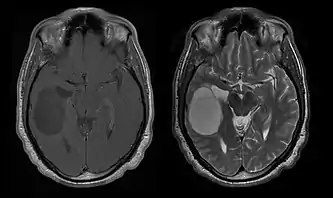

Computertomografi (CT) og magnetisk resonansbilleddannelse (MRI) kan effektivt påvise en neoplasi i hjernen. MR er mere følsom end CT til at identificere læsioner, men har kontraindikationer for patienter med pacemakere, inkompatible proteser, metalclips og andre. CT er fortsat den foretrukne metode til at påvise forkalkninger i læsioner eller knogleerosion af kaloten eller bunden . Brugen af kontrastmidler, som er ioderede i tilfælde af CT og paramagnetiske (gadolinium ) i tilfælde af MR, tillader erhvervelse af information om vaskularisering og integritet af blod-hjerne-barrieren, en bedre definition af den tumorøse tumor sammenlignet til det omgivende ødem og generering af hypoteser om graden af malignitet . Den radiologiske undersøgelse giver også mulighed for en vurdering af de mekaniske virkninger og deraf følgende ændringer i hjernestrukturer som følge af tumoren, såsom hydrocephalus og brok, hvis virkninger kan være dødelige. Til sidst, som forberedelse til operation, kan denne diagnostik bruges til at bestemme placeringen af læsionen eller infiltrationen af tumoren i vitale områder af hjernen. Til dette formål er MR mere effektiv end CT, fordi den kan give tredimensionelle billeder.

Computertomografi af hjernen viser typisk en vævsmasse, der kan forstærkes af begge kontraster. På CT forekommer lavgradige gliomer sædvanligvis isodense til det normale parenkym og viser derfor muligvis ikke kontrastforstærkning. På samme måde er læsioner i den bagerste kraniale fossa svære at identificere på CT. Følgelig er resultaterne af en sådan tomografi alene ikke altid tilstrækkelige til diagnostiske formål. I tvivlstilfælde er brugen af den mere følsomme magnetiske resonansbilleddannelse afgørende.

På-MRI viser en intrakraniel tumor som en massiv læsion, der kan blive mere selvlysende efter brug af kontrastmidlet. Der er dog altid en signalanomali i-Magnetisk resonansbilleddannelse, som indikerer tilstedeværelsen af neoplasi eller vasogent ødem. Sædvanligvis er øget luminescens (kontrastforbedring) tegn på en tumor af en højere grad af malignitet. En kontrastring er karakteristisk for glioblastom, hvor den selvlysende del svarer til den vitale del af den ondartede tumor, og den mørkere del-hypointense område svarende til vævsnekrose.

Patienter lider af en række karakteristiske symptomer på en fokal eller multifokal massiv læsion. MR viser sædvanligvis tumorer med homogen kontrastforøgelse i den dybe periventrikulære hvide substans. Multifokalitet og inhomogen forbedring er typisk for patienter med et svækket immunsystem. Analyse af CNS-lymfom er ekstremt vigtig i differentialdiagnosen af hjerneneoplasi. Det skal bemærkes, at administration af kortikosteroider kan føre til fuldstændig forsvinden af forstærkningen, hvilket gør diagnosen af læsionerne vanskelig. Hvis CNS-lymfom skal overvejes i differentialdiagnosen, bør kortikosteroider derfor undgås, medmindre masseeffekten forårsager et alvorligt og umiddelbart problem hos patienten.